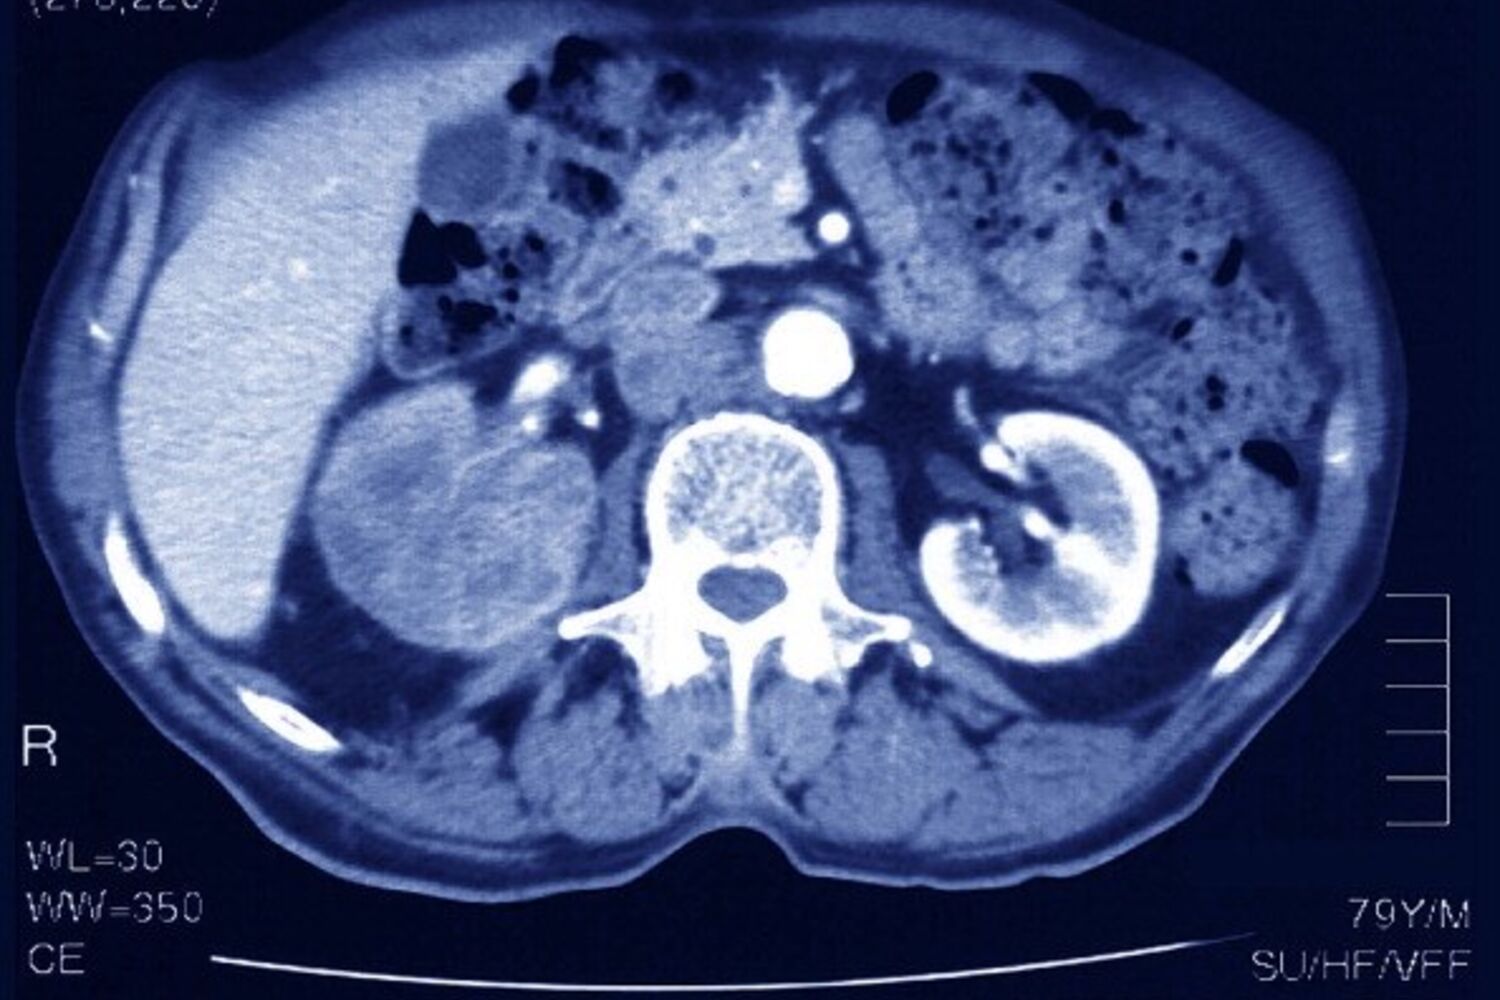

Cancro do Rim: Saiba tudo sobre este carcinoma

O cancro do rim foi o 18.º cancro mais frequente em Portugal em 2020. De acordo com os últimos dados, em 2018 foram diagnosticados 1301 novos casos e 507 óbitos relacionados à doença, cerca de 1,8% de todas as mortes por cancro em Portugal.